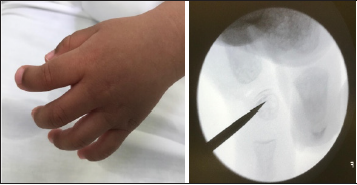

On the date of the surgery, the patient was placed under general

anesthesia in the supine position. A mid-axial incision was made

down to the level of the middle phalanx, which had a trapezoidal

shape. C-arm images and gross photos were obtained before the

start of the procedure (Figure 1). The osteotomy site was then

Figure 1: (a) Gross image of clinodactyly with delta

phalanx of the left index finger prior to the start of

the procedure

(b) Intraoperative fluoroscopic image of the delta

phalanx of the left index finger